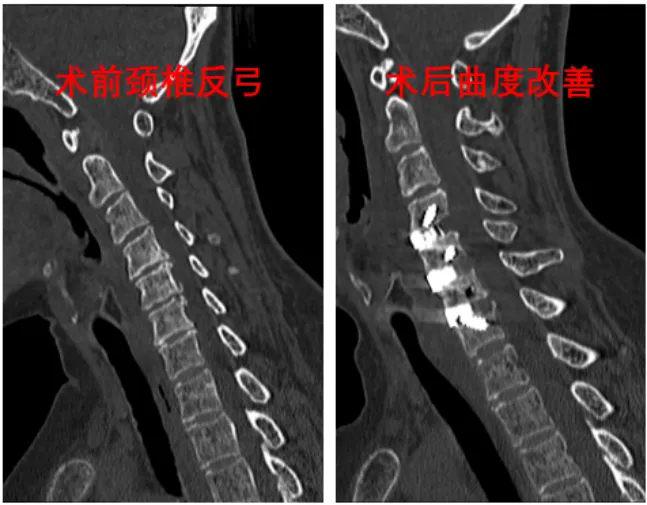

该患者长期受多节段双侧症状神经根型颈椎病困扰,经我院骨五科诊断,决定采取颈椎前路三节段颈椎间盘切除零切迹融合器植入固定手术进行治疗。该手术以往都是在肉眼直视下进行,手术切口会根据手术节段的增加进行延长,对患者的创伤也相应增加。

据骨五科副主任任伟剑介绍,为减小患者创伤,提高微创及安全性,我院在我省率先引进LUSE内镜辅助系统来辅助手术,实行三节段的颈椎减压,仅需要3厘米长度的切口(比肉眼下减压减小将近一半长度),高清内镜便可将切口内的视野进行清晰放大,还能有效减少术中气管牵拉的损伤,减压更彻底更安全,医生通过显示屏幕即可实施手术操作。

术后,患者上肢不适症状逐渐消失,经复查显示压迫症状解除。